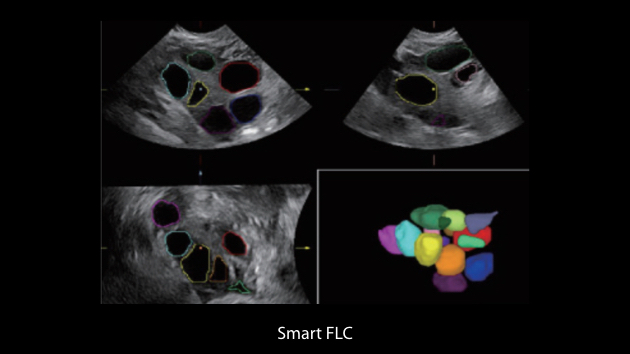

Nuewa I9? ??? ???? ?? ??? ?? ??? ???? ?? ??? ???? ???? ??? ?????. ??? ??? ??? ?? ????? ?? ???? ???? ???? ???? ??? ???? ??? ??? ???? ??? ???? ??? ?? ?????.

ZST+ ???? ???? ??? ???? ??? ?????. ??? ????? ??? ? ???? ?? ??? ?? ????? ?????. ?? ???, ?? ???, ?? ??? ?? ?? ?? ??? ??? ???? ???? ??? ?? ??? ?? ???? ?? ??? ?? ??? ?????.